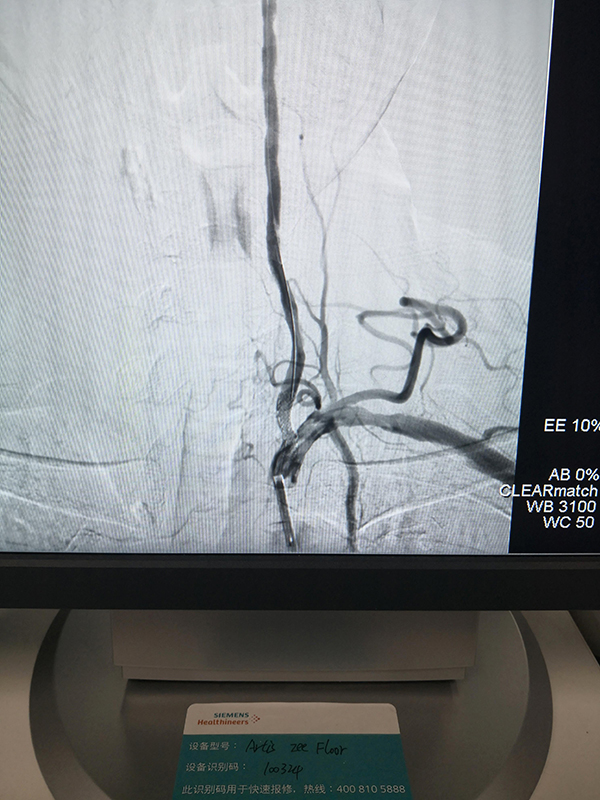

術后影像

因為及時溶栓,所以患者在轉診的路上意識便有所恢復,溶栓有效;到達柳州市人民醫院后,患者通過綠色通道直達介入室,根據患者病情進行急診取栓及支架植入手術,患者術后立即恢復清醒,四肢活動能力及語言能力恢復正常。